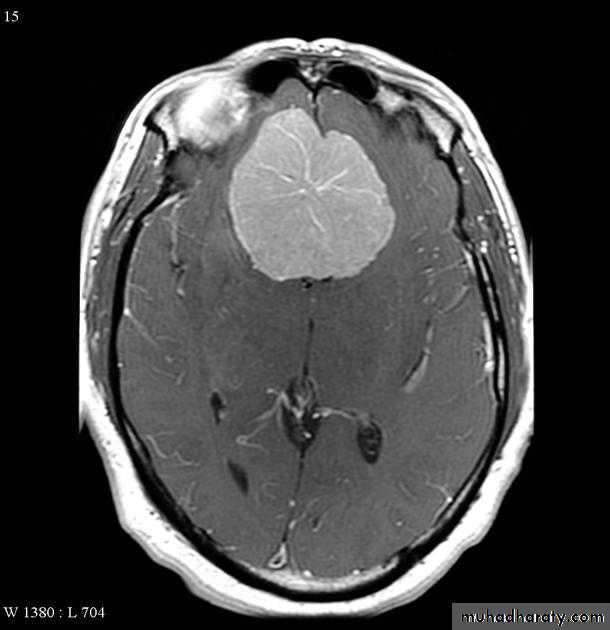

Meningioma:

• Arise from the meninges of the vault, falx, or tentorium (extra-axial)• Characteristic sites, the commonest being the parasagittal region, over the cerebral convexities, and the sphenoid ridges

• Unenhanced CT scan, a meningioma is slightly denser than the brain

• The tumour shows marked enhancement post contrast injection

• Sclerosis and thickening of the adjacent bone.